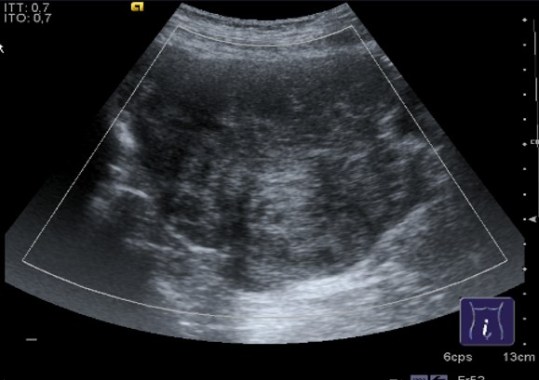

Aspecto ovárico niña neonatal.

En niñas recién nacidas podemos encontrar este aspecto en el ovario por hormonas maternas, se resuelven meses después.